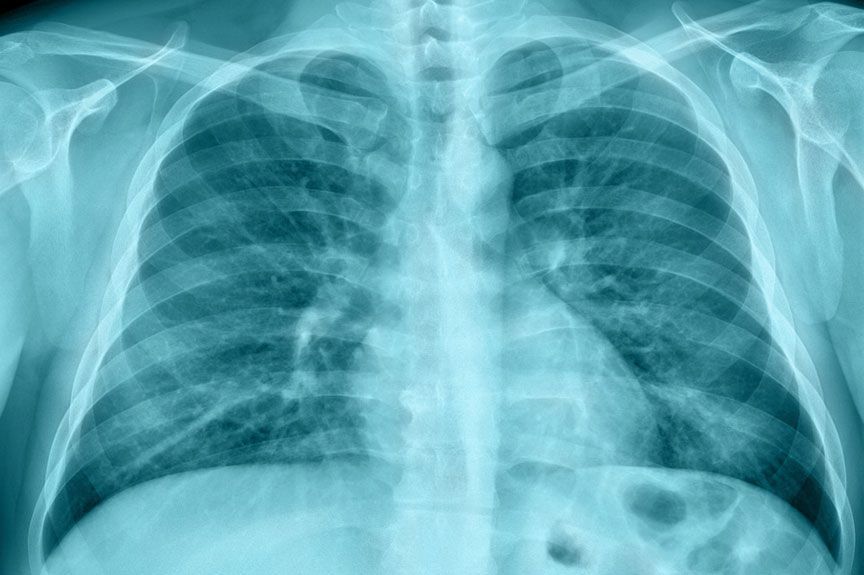

El Dr. Díaz Toledo es un especialista en neumología con acceso a tecnología de vanguardia, incluyendo pruebas de función pulmonar y estudios de imagen para realizar diagnósticos detallados para afecciones como asma, bronquitis, neumonía, EPOC